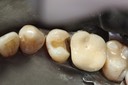

Photos of Clinical Operations

Drs. Peter Kearney, Terry McKay, John St. Germain, and Laurie Vanzella - Mentors